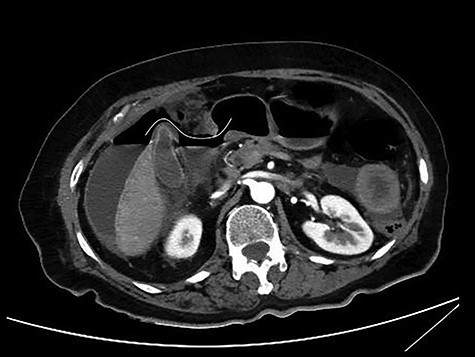

The patient was afebrile but hemodynamically unstable, with 115 bpm and a systolic pressure of 80 mmHg on presentation. Clinical examination revealed abdominal distension, diminished bowel sounds and severe tenderness with peritoneal signs in all of the abdominal quadrants. Her laboratory blood examination showed elevated number of neutrophils (7.77 K/μl), elevated C-reactive protein value (82.46 mg/dl) and decreased Na+ (119 mEq/l). After initial resuscitation, a computed tomography (CT) scan was performed. It showed free abdominal air and fluid in the peritoneal cavity, indicating an intestinal perforation (Figs 1–3).

CT scan with iv and without per os contrast media administration: communication of free air with stomach (line).